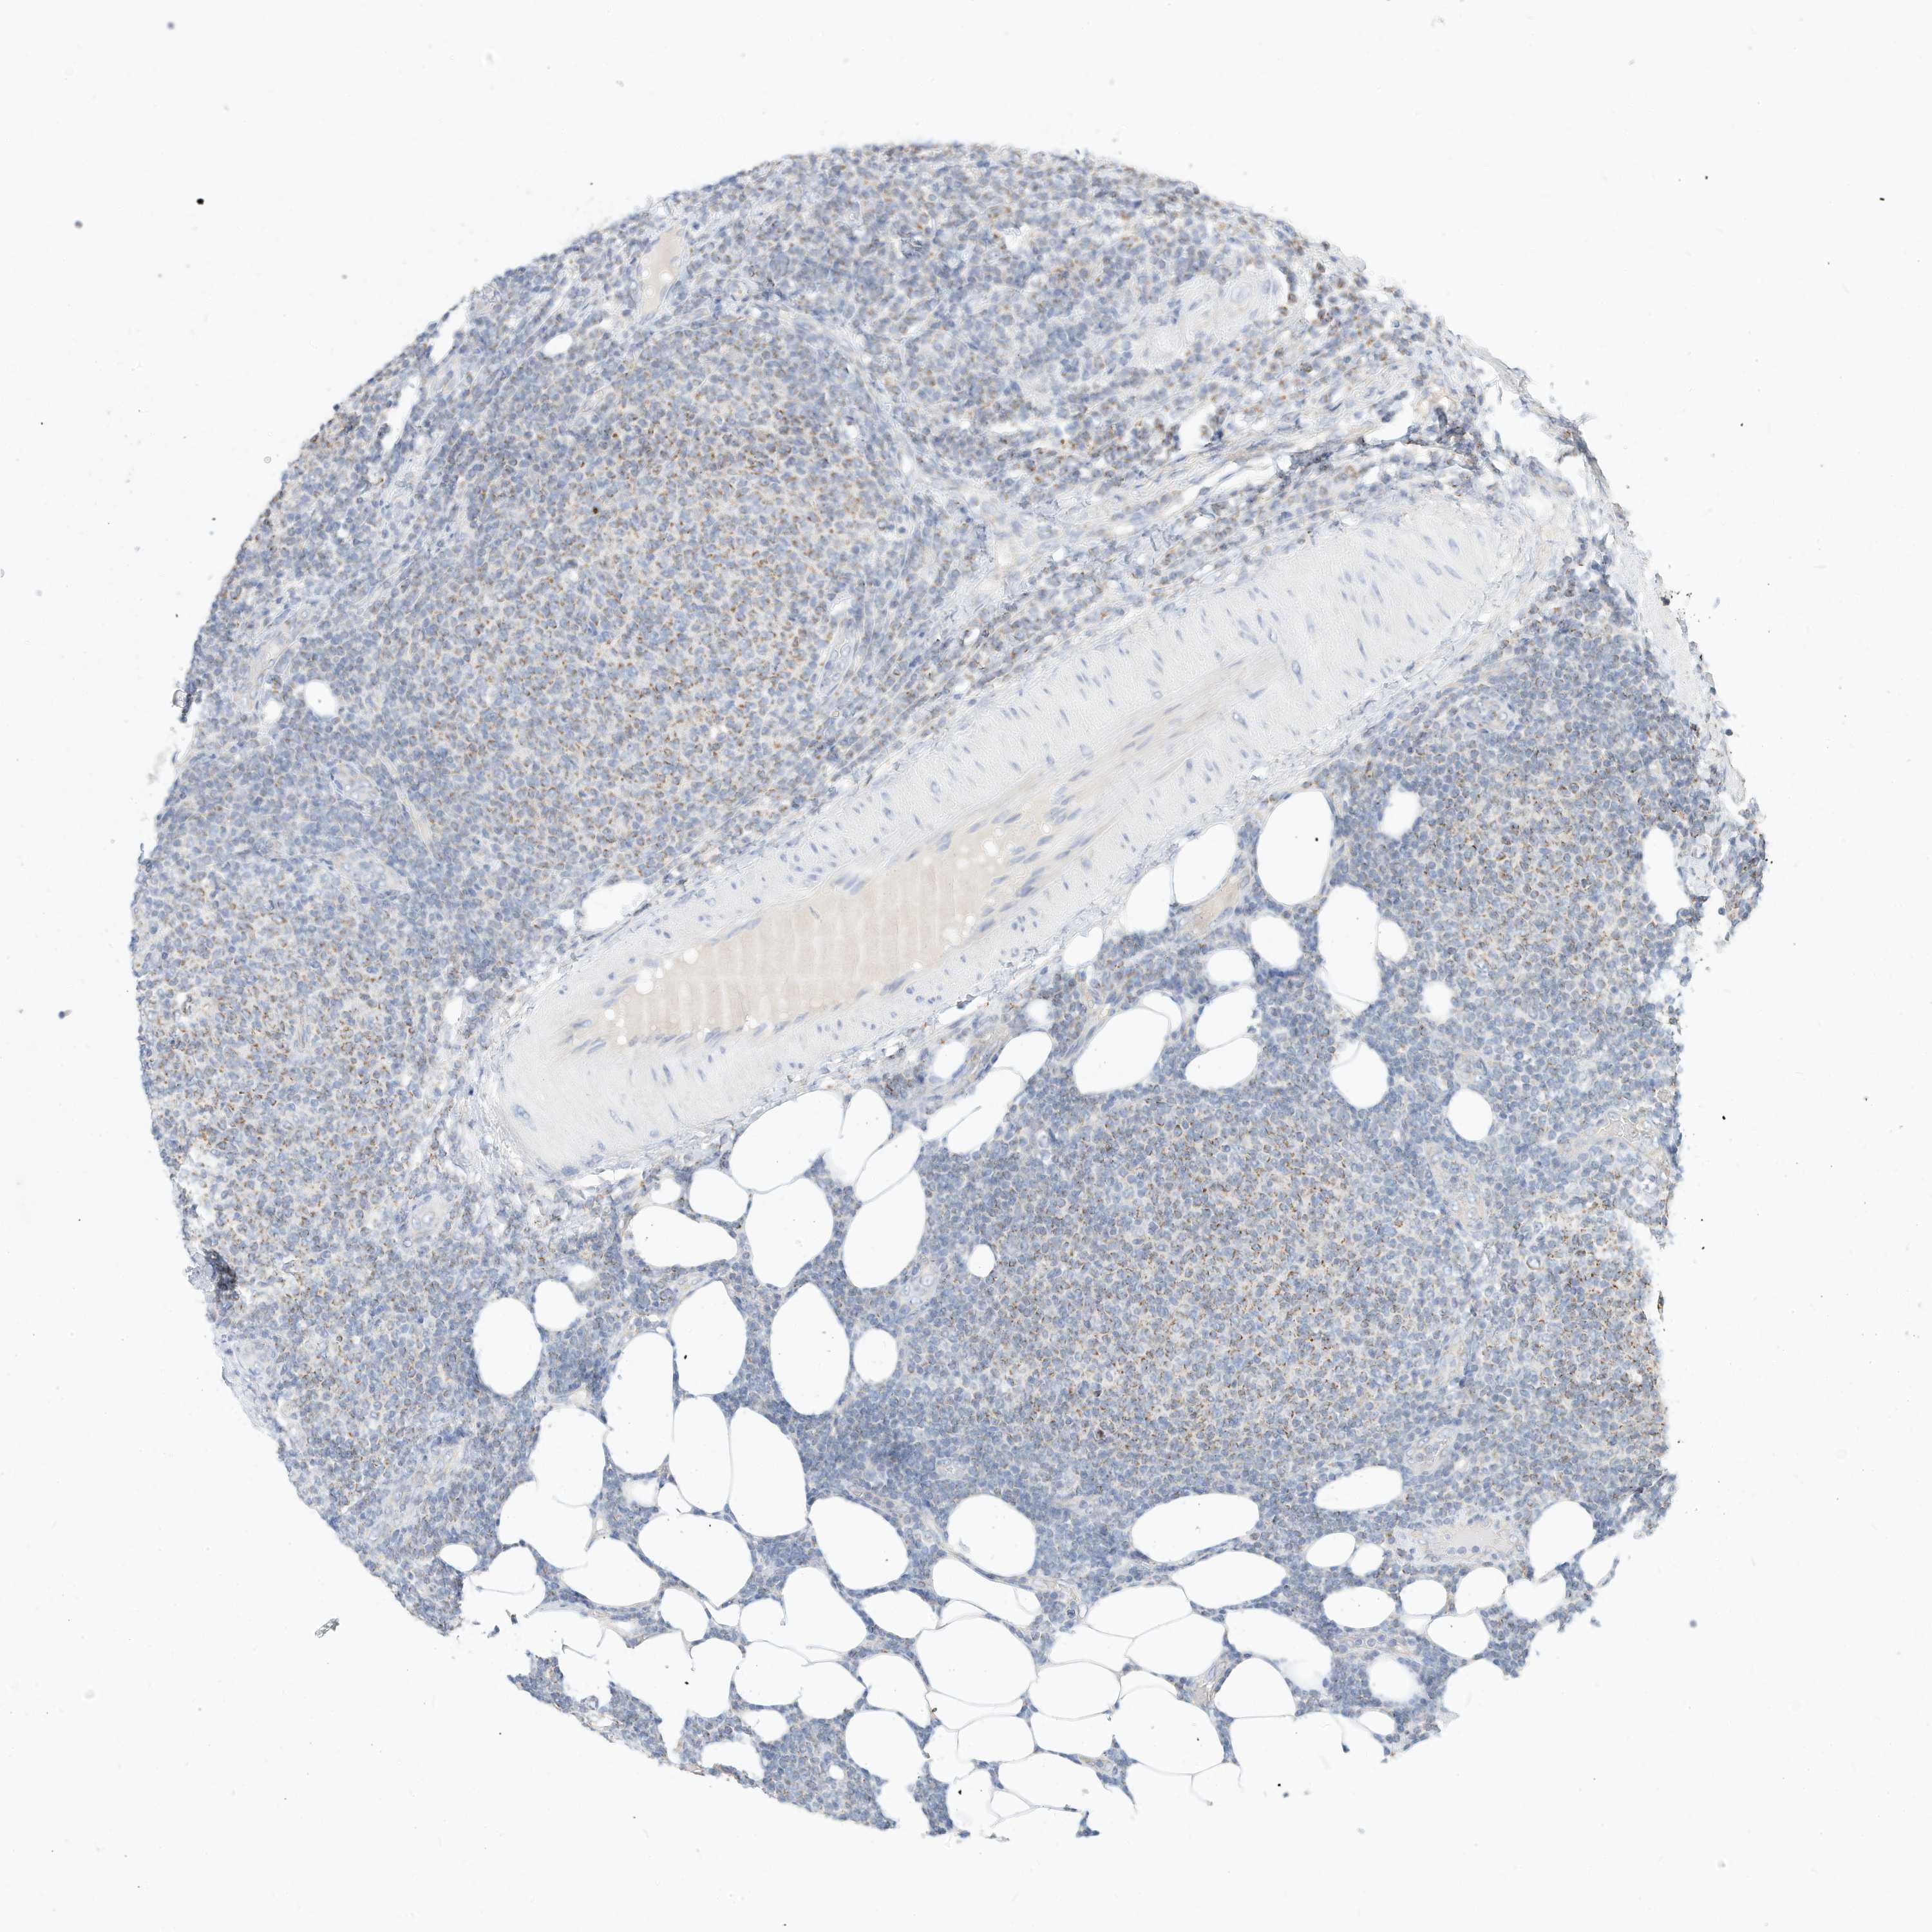

LYMPHOMA - Protein expressioni

A mouse-over function shows sample information and annotation data. Click on an image to view it in a full screen mode. Samples can be filtered based on level of antibody staining by selecting one or several of the following categories: high, medium, low and not detected. The assay and annotation is described here.

Antibody stainingi

Antibody staining in the annotated cell types in the current human tissue is reported as not detected, low, medium, or high, based on conventional immunohistochemistry profiling in selected tissues. This score is based on the combination of the staining intensity and fraction of stained cells.

Each image is clickable and will lead to virtual microscopy that enables deeper exploration of all samples and also displays staining intensity scores, fraction scores and subcellular localization as well as patient and tissue information for each sample.

Antibody HPA030345

Staining

High

Medium

Low

Not detected

Intensity

Strong

Moderate

Weak

Negative

Quantity

>75%

75%-25%

<25%

None

Location

Nuclear

Cytoplasmic/membranous

Cytoplasmic/membranous,nuclear

Hodgkin's disease, NOS

Malignant lymphoma, non-Hodgkin's type, High grade

Malignant lymphoma, non-Hodgkin's type, Low grade